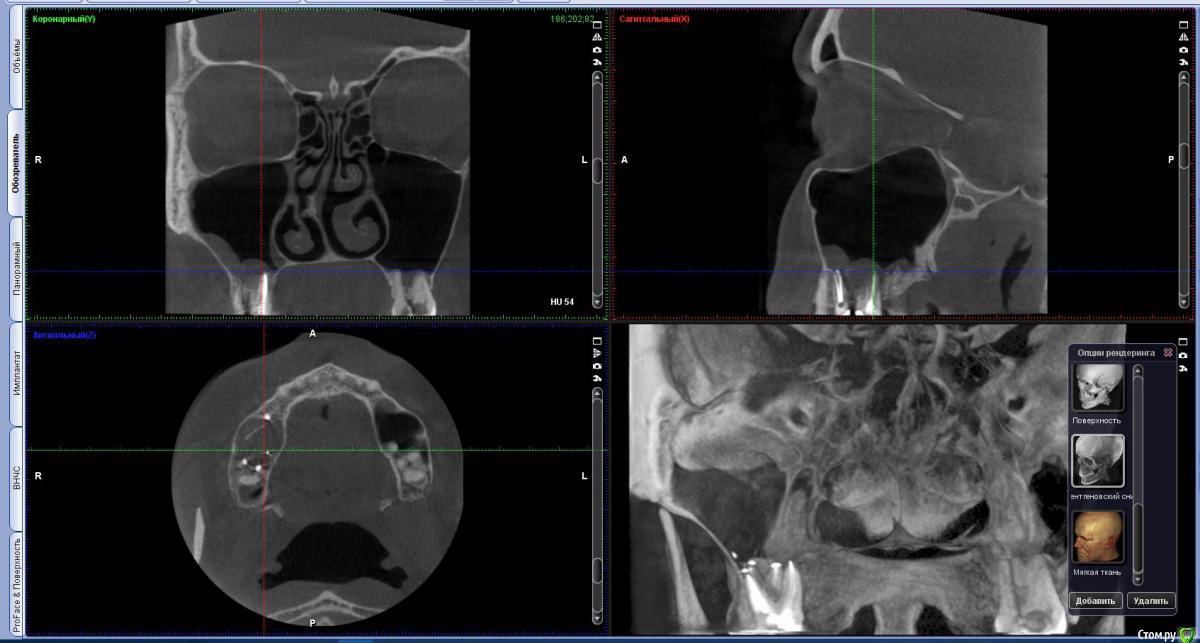

vicTORYa Опубликовано 24 мая, 2016 Поделиться Опубликовано 24 мая, 2016 Здравствуйте.В сентябре 2015 года лечила зубы с правой стороны.Снимок до леченияЛечили нижние 4,5,6,7,8 и верхние 3,4,5,6,7,8 зубы справа. В 5 и 7 верхних зубах случилась перфорация пазухи, врач поставил ультракал на месяц. Остальные зубы запломбировал постоянными пломбами, в каналы гуттаперчю поставил.В октябре пришла долечить 5 и 7 зубы. 5 запломбировали, а в 7 обнаружилась перфорация корня, врач запломбировал этот перфорированный канал какой-то специальной пастой (названия не помню). Два верхних и три нижних подготовил под коронки. Коронки решили ставить позже.Всё ждала, когда боль пройдет, но в некоторых зубах она так и не прошла, на тот момент при нажатии на зубы или постукивание болели 5, 6, 7 верхние (кажется 8 тоже), нижний 7 и немного ныл 5 нижний. Сделала панорамный снимок и пошла к врачу, он направил к ЛОРу так как увидел пятно в пазухе.Снимок на тот моментЛОР послал на КТ пазух.Сказал, что это кистозно-полипозное образование и его нужно удалять.Так ничего и не делала, оставила ситуацию в подвешенном состояние так как я в полной растерянности.На данный момент болят при постукивание верхние 5,6,7, 8 но совсем немного, при нажатие 6,7. Нижний 7 болит при нажатий и постукивание, немного 5 (и как будто ноющая боль бывает).Свежий снимок.Помогите пожалуйста разобраться. Что с этими зубами? Почему они продолжают болеть? Насколько большая проблема материал, выступивший за предел корня? Нет ли вокруг него воспалительного процесса? И что мне с ними делать дальше? Одевать ли коронки? Или может какие-то из них вообще подлежат удалению? Что с пазухой? Если нужны какие-то другие срезы из КТ могу выложить. Заранее спасибо. Ссылка на комментарий

Паращук Роман Опубликовано 24 мая, 2016 Поделиться Опубликовано 24 мая, 2016 В верхних зубах материал за пределами корня и скорее всего в пазухе. Может стать причиной воспалительных процессов или усугубить их,или поддерживать. В нижней 7ке выведенная гуттаперча за пределы канала. Если есть проблемы,то их нужно решать или организм решит их за вас. В верхних зубах эндоскопически через носовой ход,в нижнем попробовать через каналы,если нет хирургически. Ссылка на комментарий